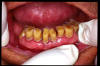

CM Ultimos dientes remanentes: los caninos